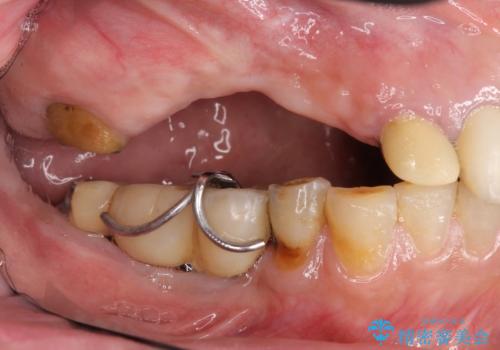

- 他院で1本インプラントを入れたまま治療に通うことができなくなり、途中からの治療を希望され来院されました。

既に埋入されているインプラントは位置が悪いのでそのまま骨内に留置することとし、新たに咬合機能を回復すべく3本のインプラントを埋入すると同時に吸収した骨幅を増やし、安定してインプラントで噛める環境整備を目指します。